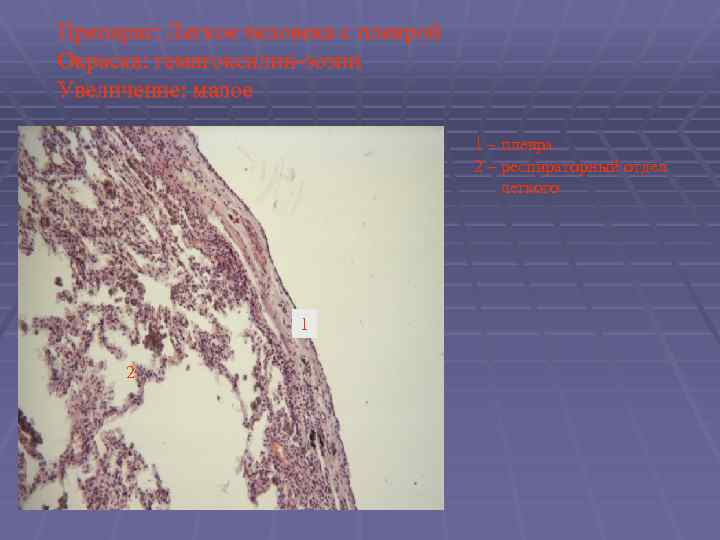

Препарат: Легкое человека с плеврой Окраска: гематоксилин-эозин Увеличение: малое 1 – плевра 2 – респираторный отдел легкого 1 2